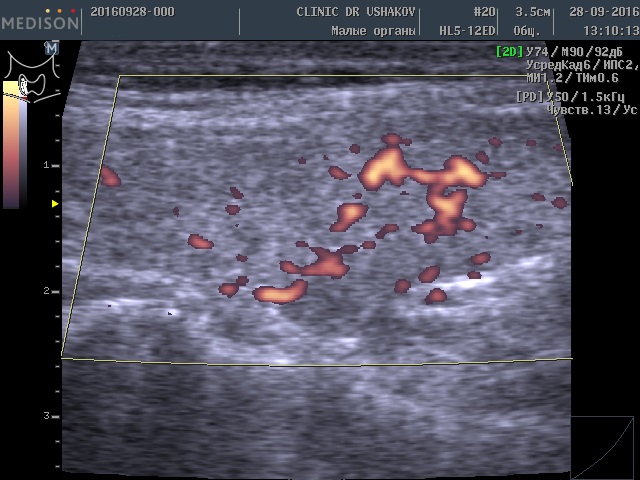

Такое более интенсивное усвоение организмом щитовидных гормонов (Т4 и Т3) вынуждает сильнее заставлять щитовидную железу производить эти гормоны. Избыточная стимуляция происходит с помощью гормона ТТГ (из гипофиза) и шейной части периферической нервной системы. Нервные клетки из нервных центров направляют свои увеличенные стимулы к ткани щитовидной железы, заставляя интенсивнее производить гормоны, и одновременно с такой же силой активизируют кровоток внутри железы, стремясь при этом доставить к ткани железы больше продуктов (для питания и образования гормонов). Вот почему у этой пациентки при УЗИ в нашей Клинике мы выявили умеренное усиление кровотока (рис. 1 и 2). Это заметно на снимках, где в специальном режиме для оценки сосудов (ЭДК) определяется увеличенное количество красных элементов (преимущественно увеличенного размера). Такая картина УЗИ не редко встречается при малом или умеренном гипертиреозе (с тиреотоксикозом), который врачи называют «повышением функции щитовидной железы».

Рисунки 1 и 2. Пациентка В., 32 г. левая и правая доли щитовидной железы в режиме ЭДК. Кровоток умеренно усилен в обеих долях (обозначен красным цветом).